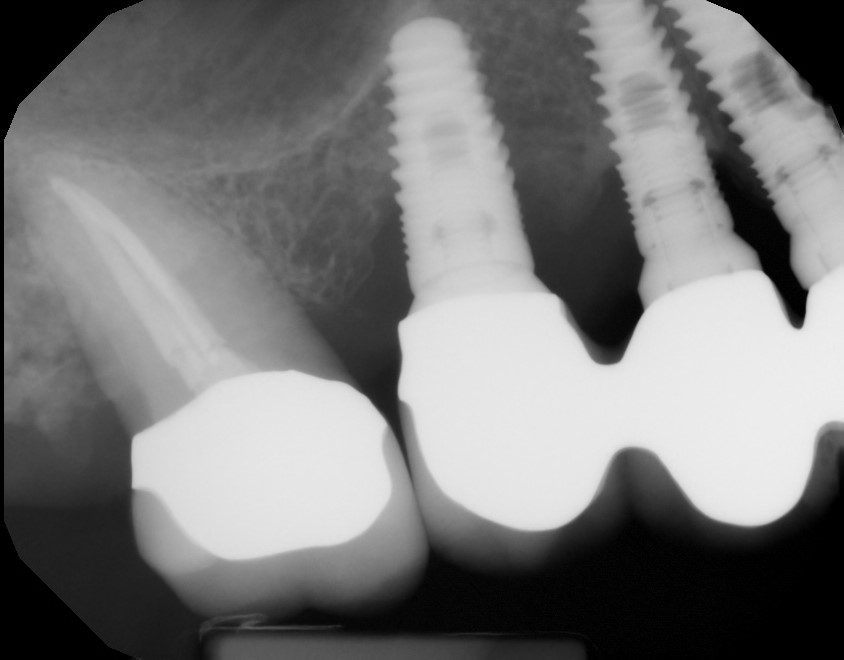

This mouth had recession on just one tooth with very little bone to support the tooth. The area needed support and thickness. The tissue was placed and the area now has thicker tissue to withstand the forces that the patient needs to place on it.